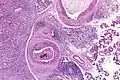

| Low magnification micrograph of a salivary duct carcinoma with characteristic comedonecrosis (left of image) adjacent to normal parotid gland (right of image). H&E stain. | |

Very low mag.